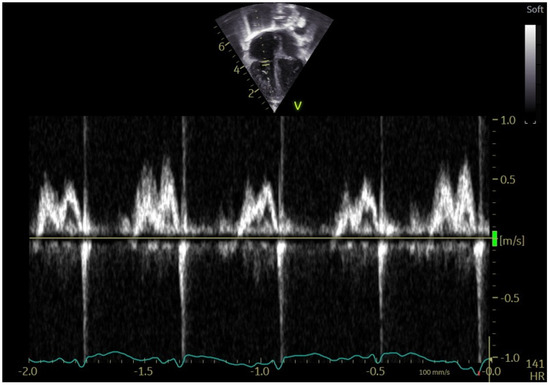

Echocardiographic Markers of Right Ventricle Diastolic Dysfunction in Neonates and Infants with Congenital Heart Disease

Background: Assessing right ventricular (RV) diastolic function by echocardiography in pediatric patients remains complex, particularly in congenital heart disease (CHD) characterized by RV pressure overload. The geometric peculiarities of the RV, respiratory influences, and age-dependent maturational changes complicate interpretation of Doppler-derived indices. This study aimed to characterize tricuspid valve (TV) pulsed-wave Doppler E/A inflow patterns in infants with CHD and RV pressure overload, evaluated shortly after surgical or percutaneous intervention. Methods: Echocardiographic analysis included TV E- and A-wave velocities obtained by pulsed-wave Doppler and measurement of E-wave deceleration time (EDT). Beat-to-beat variability was quantified over three consecutive cardiac cycles. Data were compared with a large cohort of age-matched healthy children. Results: Fifty-seven infants with CHD (35 pulmonary stenosis; 22 tetralogy of Fallot), examined 12–48 h post-intervention, were compared with 134 healthy controls. CHD patients showed markedly reduced beat-to-beat variability of both E- and A-wave velocities (p < 0.001 and p = 0.007, respectively). A three-beat E/A inversion pattern—common in neonates but variable in healthy infants—was consistently observed in CHD patients (p < 0.001). A-wave velocities were significantly higher (p < 0.001), whereas E/A ratios (p < 0.001) and EDT values (p = 0.010) were significantly lower compared with controls. Conclusions: Infants with CHD and RV pressure overload exhibit a characteristic Doppler pattern consisting of E/A ratio inversion, reduced beat-to-beat variability, increased A-wave velocity, and shortened E/A ratio and EDT. These findings may serve as practical and reproducible indicators of RV diastolic dysfunction in the early post-intervention period in neonates and infants. Full article